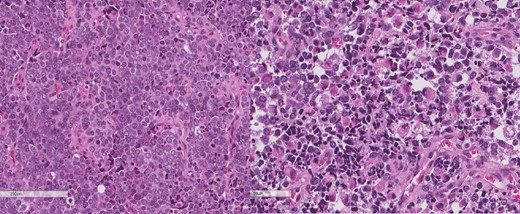

A review of the previously resected esophageal tumor revealed the presence of both epithelial and sarcomatous components. The epithelial component was composed of moderately to poorly differentiated adenocarcinoma, while the sarcomatous component showed hyperchromatic round to spindle cells with scant cytoplasm and frequent mitoses (Figs 3–6). The intrathoracic tumor showed a similar morphology as the sarcomatous component of the esophageal tumor, with focal rhabdomyoblastic differentiation (Fig. 7). The latter was strongly positive for desmin, myogenin, and MyoD1 and was focally positive for synoplastin, CD56, CD 10, and FL1.

Low power magnification of the esophageal tumor exhibiting the epithelial (left) and the sarcomatous components (right).